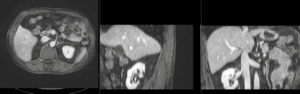

this is a pre-op CT + contrast reference image. All images are aligned into this space lleft this is the pre-op MRI we seek to align with the CT

fixed image/target moving image

• reference/fixed : pr-op CT, 0.95 x 0.95 x 5 mm voxel size

• moving: intra-op MRI, 0.78 x 0.78 x 2.5 mm axial,

unregistered MRI & CT